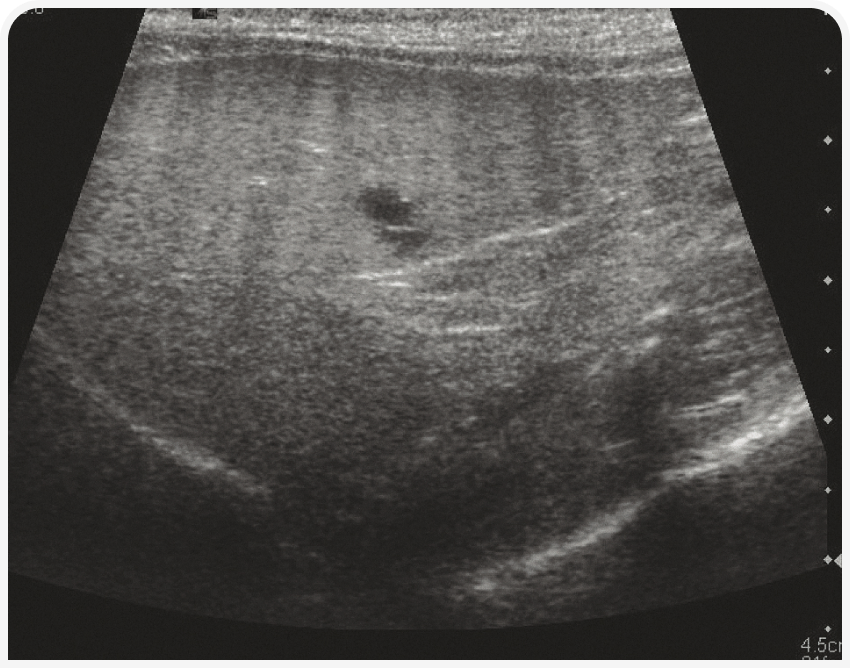

Паренхима печени однородная, слегка зернистой эхотекстуры, гипоэхогенна относительно серповидной жировой подушки и селезенки (Рисунок 3) и изо- или гипоэхогенна относительно правой почки (1). Контуры печени должны быть гладкими и ровными, очерченными тонкой гиперэхогенной капсулой. Разделение долей печени должно быть четким, если только в брюшной полости нет свободной жидкости. Печеночные вены легко визуализируются в паренхиме печени в виде трубчатых анэхогенных структур, а ветви воротной вены отличаются от системных вен гиперэхогенными стенками. Кроме того, по степени видимости портальных сосудов можно оценивать эхогенность ткани печени.

В основном при ультразвуковом исследовании можно выявить изменение размеров (чаще всего гепатомегалию) и эхогенности печени или наличие в ней узелка или объемного новообразования. Ультразвуковое исследование позволяет с высокой чувствительностью обнаруживать изменения паренхимы, но оно неспецифично, поэтому любые изменения следует интерпретировать с учетом клинических проявлений. Например, гиперэхогенную гепатомегалию на фоне желтухи у кошек можно с высокой вероятностью считать проявлением липидоза, а у собак с диабетом считать вариантом нормы. При этих двух заболеваниях паренхима печени также будет разрежена (Рисунок 4). Острый гепатит может характеризоваться гипоэхогенной гепатомегалией, а хронический – гетерогенностью тени и неровными краями печени.